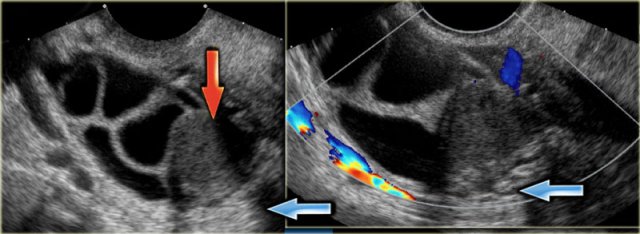

The transvaginal ultrasound images show a small complex ovarian cyst with wall vascularity on power Doppler analysis.

The characteristic circular Doppler appearance is called the 'ring of fire'.

Note, there is good through-transmission and no internal vascularity, consistent with a, partially involuted, corpus luteum cyst.

Corpus luteum cyst Corpus luteum cyst

Another case with the typical the 'ring of fire' on ultrasound.

At pathologic examination the collapsed bloody cyst can be clearly seen.